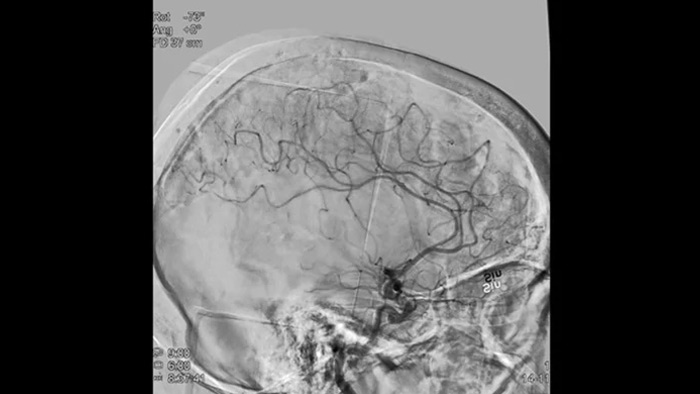

Четкие изображения при помощи 2D DSA с использованием технологии ClarityIQ

2D DSA с использованием технологии ClarityIQ

Технология ClarityIQ применяет опцию автоматической компенсации артефактов движения во время проведения DSA в режиме реального времени, чтобы создавать четкие изображения сосудов. Это способствует принятию верных решений во время операций по лечению инсульта.